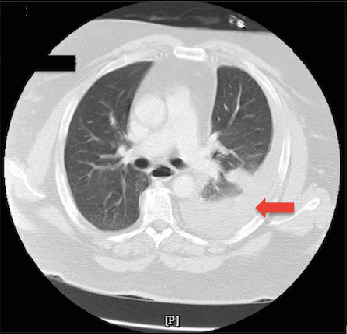

Hemothorax, the accumulation of blood in the pleural space, is most frequently linked to chest trauma but can occasionally result from nontraumatic causes such as persistent or forceful coughing. Cough-induced rib fractures are rare, with an even less frequent association with hemothorax. We describe a case involving a 57-year-old male who presented with a worsening cough and left-sided pleuritic chest pain despite prior antibiotic and symptomatic treatment. Initial imaging revealed a minimally displaced 10th rib fracture, left-sided atelectasis, and trace pleural effusion. During his hospital stay, he developed acute respiratory distress and increased chest pain, with repeat imaging revealing a large left-sided hemothorax. Chest tube placement drained 1100 mL of blood, supporting the diagnosis of hemothorax, as evidenced by clinical presentation and imaging, despite the absence of fluid analysis. The patient's condition improved following the intervention, and he was discharged in stable condition without recurrence of hemothorax on follow-up imaging. This case highlights the rare association between cough-induced traumatic rib fractures and delayed development of hemothorax. While rib fractures typically result from blunt trauma, they can also occur from stress or repetitive coughing. Complications such as hemothorax are uncommon but potentially life-threatening. The interval development of hemothorax, as seen in this patient, underscores the importance of serial monitoring in cases of rib fractures with ongoing symptoms. Clinicians should maintain a high index of suspicion for hemothorax in patients presenting with rib fractures and persistent cough, particularly in the context of worsening respiratory symptoms or pleuritic chest pain. Early recognition and timely intervention are critical to optimizing outcomes and mitigating the risks of rapid clinical deterioration.